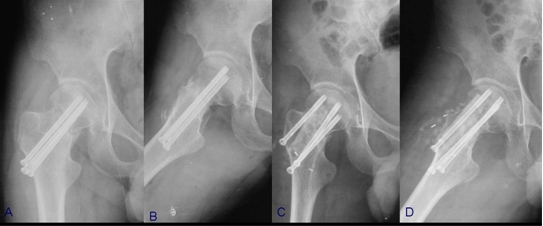

骨折端充分显露后,可直视下清理骨折端至新鲜断面,通过牵引、内旋下肢间接复位或撬拨骨折端直接复位,随后多枚克氏针临时固定,透视下见骨折端复位满意后进行最终的内固定,股骨颈骨折可采用多枚平行拉力螺钉或锁定钢板,同时行吻合血管的游离腓骨移植(图5),粗隆间骨折可根据其骨折类型选用锁定钢板或髓内钉,通常无需植骨(图6)。

图5 股骨颈骨不连病例

A,B,患者术前髋部正侧位片示股骨颈骨不连;C,D,患者术后髋部正侧位

图6 股骨粗隆间骨不连病例

A, 患者术前X线(内固定术后3月);B,采用前侧入路髓内钉翻修术后